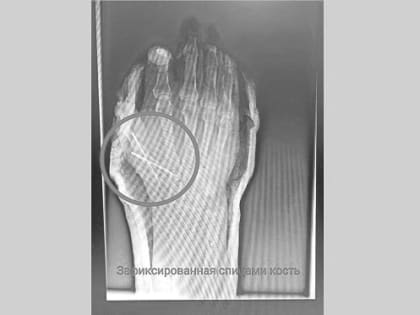

В Татарстане врачи спасли от ампутации палец 54-летнего мужчины, отрезанный болгаркой

Врачи Нижнекамской центральной районной многопрофильной больницы рассказали о спасении 54-летнего пациента, который работая на даче случайно травмировался болгаркой.